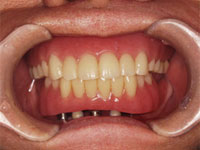

口内写真

上下ともに歯がなく入れ歯を使用しているため顎の骨が溶けてしまい歯茎が下がってしまっている。.